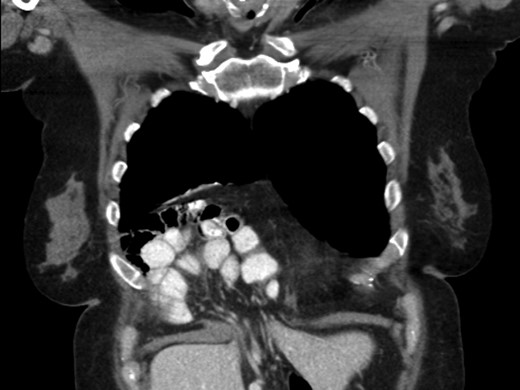

A 69-year-old female was referred to our clinic for an incidental finding of a large Morgagni hernia found on a recent CT chest scan for lung cancer screening. Patient reported occasional shortness of breath after prolonged ambulation but denied chest pain. She did have remote history of acid reflux symptoms but nothing recently. She denied issues with prematurity or issues with development as an infant, chest trauma, or MVA history. She did complain of occasional right shoulder pain but attributed this to arthritis. Denied history of heart attack, stroke, DVT, or PE. She had a 30-pack-year smoking history but quit a year prior. She was up-to-date on her colonoscopy, current within the past year. She denied hematochezia and melena, bowel habit changes or major body weight changes as well as any current abdominal pain. On examination her vitals were within normal parameters. Heart and lungs were unremarkable. Abdominal examination was soft with normal bowel sounds and nontender. Remainder of examination was unremarkable. Laboratory values included a normal CBC and BMP. A CT chest scan had demonstrated a large retroxyphoid hernia of Morgagni involving several loops of small bowel and transverse colon located in the right inferior hemithorax (Figs 1 and 2). No evidence of acute incarceration or strangulation were noted. A detailed discussion was undertaken with the patient regarding her hernia and she was consented for a laparoscopic repair with mesh.

Preoperative CT scan of chest demonstrating the wide retroxyphoid defect in the diaphragm with herniated small bowel and colon into the right inferior hemithorax.